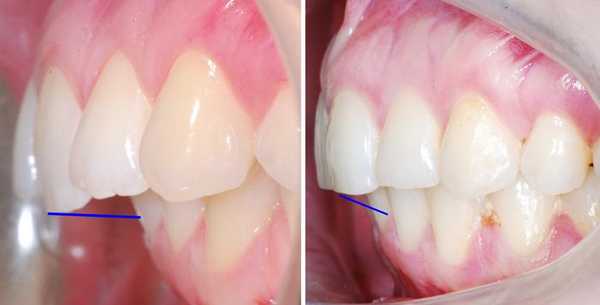

В полости рта дистальный прикус определяется по выступающим вперед верхним фронтальным зубам. В норме, при ортогнатическом прикусе, верхние резцы перекрывают нижние примерно на 1/3. При дистальной патологии между верхними и нижними резцами образуется расстояние — «саггитальная щель».

Саггитальная щель и прикус в норме